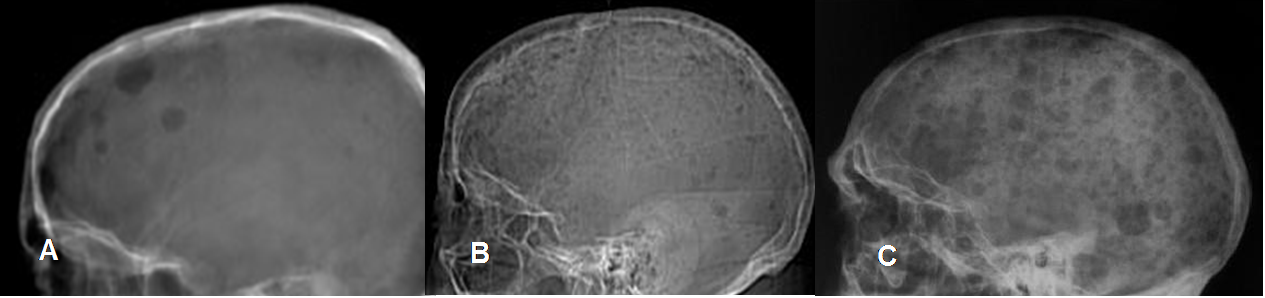

Fig 188. Mieloma.

A, B y C: Rx lateral. Espectro de hallazgos en el cráneo del mieloma, con múltiples lesiones en sacabocado y de bordes mal definidos.